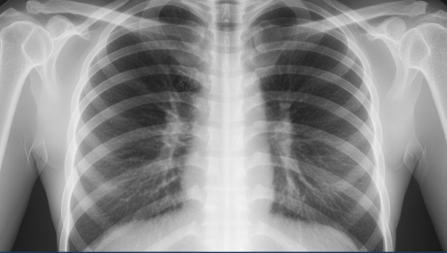

Современная медицина практически полностью отказалась от старых пленочных аппаратов в пользу цифровых технологий. Цифровая флюорография, применяемая в ведущих клиниках, обладает рядом неоспоримых преимуществ. Во-первых, это значительно сниженная лучевая нагрузка на организм пациента, что делает процедуру максимально безопасной. Во-вторых, высокая четкость изображения позволяет врачу-рентгенологу детально рассмотреть структуру легких, средостения и реберного каркаса.

В 2026 году результаты цифровых исследований мгновенно заносятся в электронную медицинскую карту, что упрощает процесс прохождения медосмотров и исключает риск потери снимка. Качественная диагностика помогает выявить не только специфические инфекционные процессы, такие как туберкулез, но и профессиональные заболевания (пневмокониозы), а также ранние стадии онкологии легких, что существенно повышает шансы на успешное лечение.